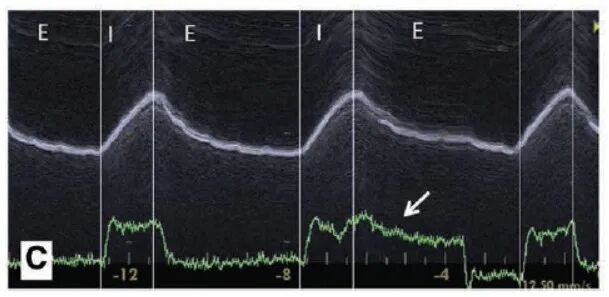

膈肌超声可用于诊断自动触发,如下图所示,绿色线为压力时间曲线,上方白色粗线为膈肌位移图像,通过分析图像可以看出,白色箭头处在无膈肌位移(即患者吸气)的情况下呼吸机存在送气,可判定为自动触发。